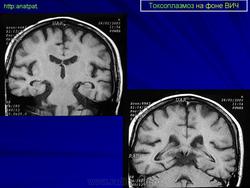

Токсоплазмоз у ВИЧ - инфицированных

Пато морфологи я. Патоморфологические изменения при приобретенном токсоплазмозе изучены в экспериментах на животных. Установлено, что в центральной нервной системе развиваются явления некротического перивентрикулита, мелкие очаги некроза в субкортикальном белом веществе. В сосудах головного мозга, мягкой мозговой оболочки и хориоидальных сплетениях отмечаются признаки серозно-пролиферативного воспаления. Обнаруживаются также глазные патологоанатомические изменения (типа ретинита, хориоидита, иридоциклита) и изменения во внутренних органах (сердце, легкие, печень, селезенка).

Врожденный токсоплазмоз чаще, чем приобретенный, приводит к летальному исходу. В головном мозге умерших обнаруживаются более или менее значительные очаги обызвествления, участки размягчения мозгового вещества, полости, заполненные жидкостью. Как правило, отмечается гидроцефалия, обусловленная воспалительной и рубцовой облитерацией водопровода среднего мозга, отверстий Люшка или других участков ликворных путей. Истон-чение вещества полушарий мозга может достигать степени их полного исчезновения.

Особенно характерна триада симптомов: хореоретинит, гидроцефалия, очаги обызвествления в головном мозге. Кроме того, отмечаются менингеальные знаки, тонические и клонические судороги, парезы, параличи, олигофрения.

Неврологические симптомы могут сочетаться с пневмонией, миокардитом, гепатоспленомегалией, с выраженной желтухой. В спинномозговой жидкости отмечается лимфоцитарный плеоцитоз (до 500 • 106 в 1 л), ксантохромия (“канареечный” ликвор). На рентгенограмме черепа обнаруживаются обызвествления в глубинных отделах головного мозга, сосудистых сплетениях. Как и приобретенный, врожденный токсоплазмоз может протекать остро, подостро и хронически.

Церебральный токсоплазмоз.

Церебральный токсоплазмоз